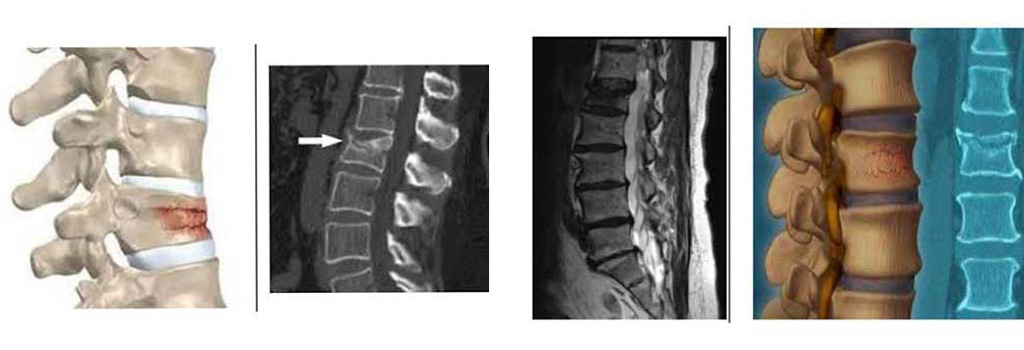

ToggleΗ διαδερμική κυφοπλαστική είναι μία μέθοδος μειωμένης επεμβατικότητας για την θεραπεία των συμπιεστικών σπονδυλικών καταγμάτων (Σ.Σ.Κ.), τα οποία είναι κατάγματα των σπονδυλικών σωμάτων που σχηματίζουν την σπονδυλική στήλη. Όταν σε ένα σπονδυλικό σώμα συμβαίνει κάταγμα, το σύνηθες ορθογώνιο σχήμα του οστού συμπιέζεται προκαλώντας πόνο. Αυτά τα συμπιεστικά κατάγματα μπορεί να συμβαίνουν σε ένα ή σε περισσότερους σπονδύλους στην σπονδυλική στήλη και είναι σύνηθες επακόλουθο της οστεοπόρωσης.

Χρησιμοποιούμε ακτινοσκοπική καθοδήγηση για να εισάγουμε δια μέσου βελόνας ένα μπαλόνι στο σπονδυλικό κάταγμα, το οποίο εκτεινόμενο ανατάσσει το κάταγμα και δημιουργεί μια κοιλότητα μέσα στον Σπόνδυλο. Η ενίσχυση των σπονδύλων που έχουν υποστεί κάταγμα γίνεται με έγχυση ειδικού σκληρυντικού υλικού στην κοιλότητα όταν το μπαλόνι απομακρυνθεί. Η χειρουργική τομή είναι περίπου 0,5 εκατοστά.

Ασθενής 76 Ετών προσήλθε με έντονους πόνους Οσφύος στα πλαίσια κατάγματος Ο1 και Ο3 .

Αντιμετωπίστηκε με Διαδερμική Κυφοπλαστική στους παραπάνω σπονδύλους.